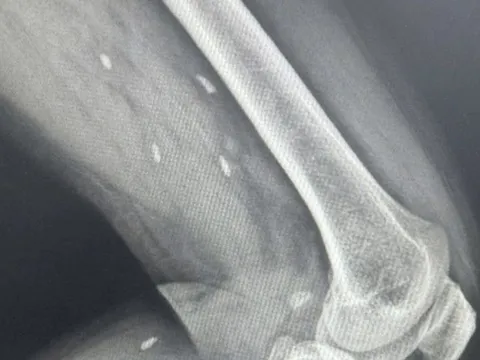

Người bệnh nhập viện trong tình trạng tiểu buốt, tiểu khó kéo dài do sỏi phát triển lớn trong bàng quang. Bác sĩ lập tức lấy ra viên sỏi kích thước tới 60x40 mm, lớn gần bằng quả trứng ngỗng.